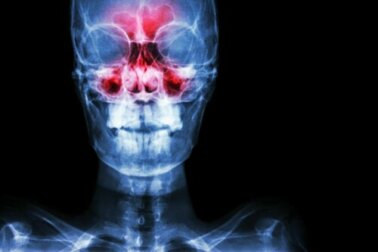

A sinusite é a inflamação dos seios paranasais, que são dois pequenos espaços ocos por onde passa o ar que circula entre os ossos do nariz. Eles são divididos em seios frontais, seios etmoidais, seios esfenoidais e seios maxilares.

Estando tudo dentro da normalidade, o ar passa sem problemas por estas cavidades. Por outro lado, quando elas sofrem algum tipo de inflamação, surgem dificuldades respiratórias e outros desconfortos, como dores que às vezes podem ser muito intensas.